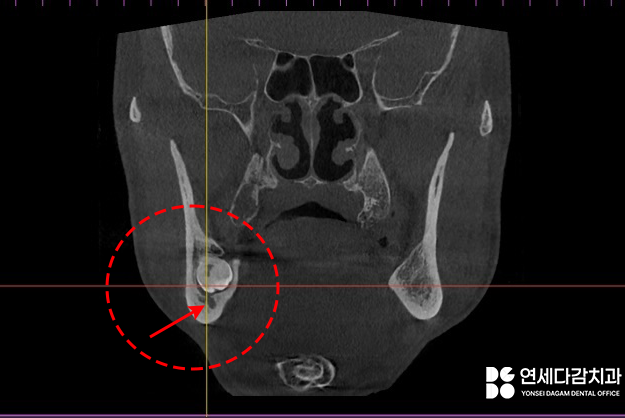

CBCT 분석 결과

신경관이랑 근접해 있습니다.

사랑니와 밀접해 있는

이것은 하치조신경으로

아래턱의 감각을 담당하는데요.

이것이 손상되면 아래턱 감각이

저하되거나 이상 감각 또는

영구적 상실이 될 수 있습니다.

또한 혈류가 풍부하게 존재하여

이를 뺀 후출혈이

심할 수도 있죠.

따라서 오금역 치과 에서

보여드린 과정처럼

신경과 치아 뿌리와의

근접도를 파악 및 분석을 하여

조심스럽게 발치를 진행하게 됩니다.